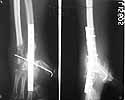

Shortened ulna and stabilised to hand using K wires. First metacarpal axially stabilised.

Primary anastomosis of vessels, tendons and nerves. Volar skin partially primarily closed and rest with a microvascular grascilus free flap to cover dorsolateral aspect. Split skin graft to cover the muscle.

I would like to give a 5 month follow up of this case.

At about two months post initial surgery, fingers were mobilised and a formal wrist arthrodesis was done along with resection of distal ulna to give some rotational movement of forearm. He was given an eight week immobilisation of wrist and then further mobilisation of fingers were given. Some of present functional pictures are attached. In the meantime the original team which treated this patient has moved out of the centre to different parts of the globe and he is continuing follow up with the available team member in this country. May be patient's persistence has given the result thus far.